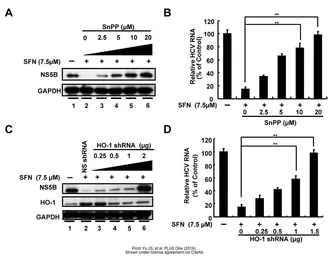

The data was published in the journal PLoS One in 2016.PMID: 27023634

The data was published in the journal PLoS One in 2016.PMID: 27023634

The data was published in the journal PLoS One in 2016.PMID: 27023634

The data was published in the journal PLoS One in 2016.PMID: 27023634

The data was published in the journal PLoS One in 2016.PMID: 27023634

The data was published in the journal PLoS One in 2016.PMID: 27023634